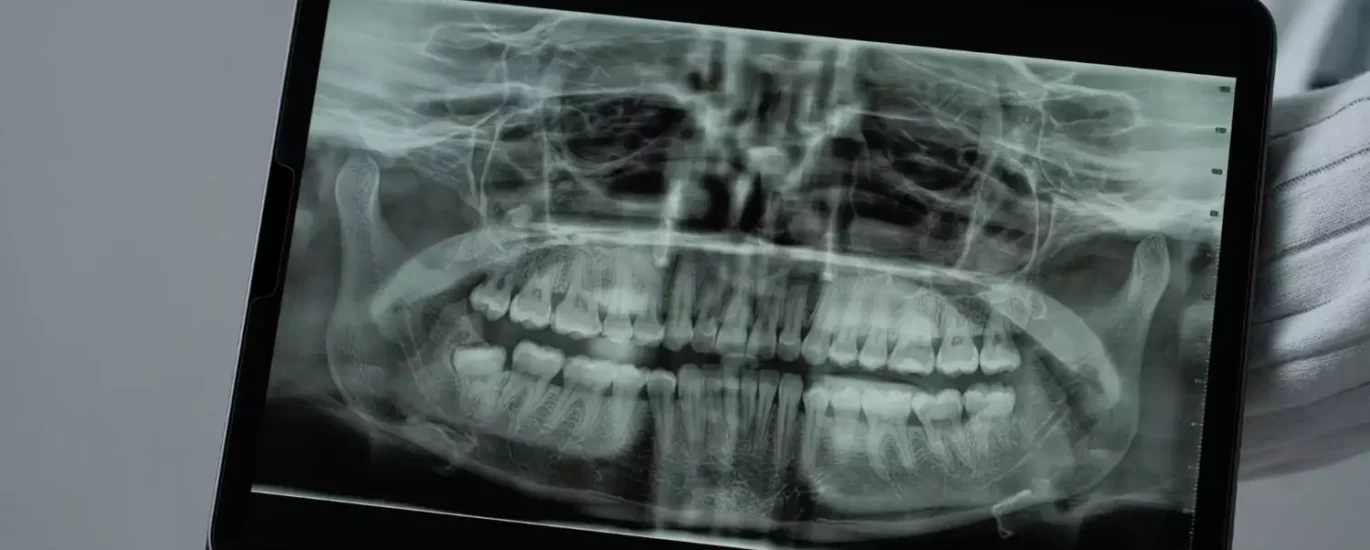

Nowoczesne zastosowania rentgenu w diagnostyce stomatologicznej stanowią istotny postęp w dziedzinie leczenia zębów. Dzięki technologii rentgenowskiej możliwe jest uzyskanie precyzyjnych obrazów struktury zębów oraz otaczających je tkanek. To umożliwia szybką i skuteczną diagnozę różnego rodzaju schorzeń. Prześwietlenie zębów kielce jest jedną z nowoczesnych usług oferowanych przez profesjonalne laboratoria stomatologiczne, umożliwiającą kompleksową ocenę stanu zdrowia jamy ustnej.

Badanie rentgenowskie, zwłaszcza w przypadku diagnostyki stomatologicznej, pozwala lekarzom na dokładne zlokalizowanie stanów zapalnych, infekcji, ubytków próchnicowych oraz ocenę struktury korzeni zębowych. Dzięki temu możliwe jest zaplanowanie odpowiedniej terapii, a także monitorowanie postępów leczenia. Nowoczesne metody rentgenodiagnostyki, takie jak cyfrowa radiografia, pozwalają na ograniczenie dawki promieniowania, co stanowi istotne zwiększenie bezpieczeństwa pacjentów.

Nowoczesne zastosowania rentgenu w diagnostyce stomatologicznej przynoszą rewolucyjne zmiany w dziedzinie opieki stomatologicznej. Zaawansowane technologie obrazowania rentgenowskiego pozwalają lekarzom stomatologom na precyzyjną diagnozę i planowanie skutecznych terapii. Rentgen w stomatologii umożliwia dokładne zobrazowanie struktury zębów, kości szczęki oraz tkanek miękkich jamy ustnej. To jest kluczowe dla trafnej oceny stanu zdrowia pacjenta.

Współczesne techniki obrazowania rentgenowskiego, takie jak cyfrowa radiografia, tomografia komputerowa stożkowa (CBCT) oraz technologie 3D, umożliwiają uzyskanie szczegółowych obrazów zębów i otaczających je tkanek. Dzięki temu lekarze stomatolodzy są w stanie wykrywać patologie, takie jak zapalenie miazgi czy choroby przyzębia we wczesnych stadiach. To natomiast umożliwia wdrożenie leczenia jeszcze zanim dolegliwości stają się poważne.

Nowoczesne zastosowania rentgenu w diagnostyce zębów odgrywają kluczową rolę w identyfikowaniu problemów zdrowotnych jamy ustnej. Jednym z najnowszych osiągnięć w tej dziedzinie jest rentgen 3D, który przynosi wiele korzyści w diagnostyce zębów. Obrazowanie 3D umożliwia lekarzom dentystom uzyskanie bardziej szczegółowego obrazu struktury zębów, korzeni i otaczających tkanek. Dzięki temu możliwe jest skuteczniejsze wykrywanie patologii, takich jak zmiany zapalne czy nowotwory. Dodatkowo, rentgen 3D pozwala na lepsze zaplanowanie zabiegów stomatologicznych, dzięki precyzyjnemu wyznaczeniu miejsca wszczepienia implantów czy określeniu stopnia zaawansowania ubytków w korzeniach zębów.